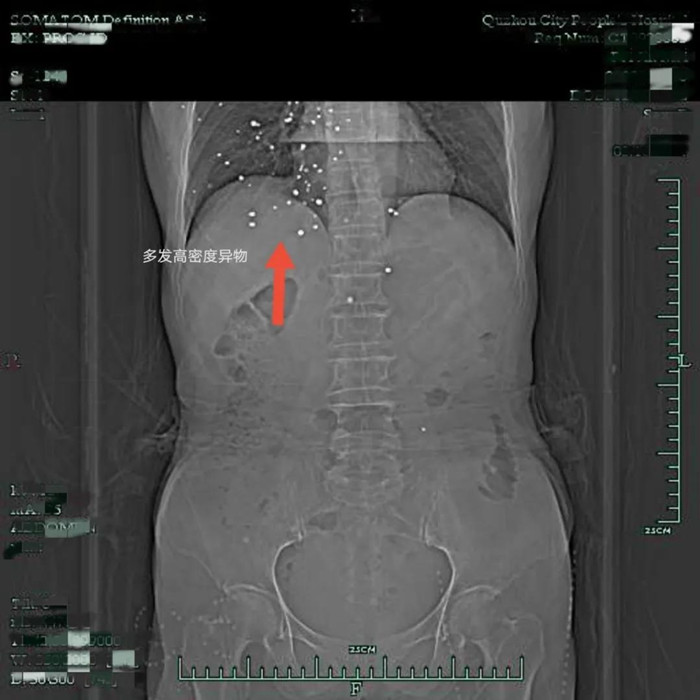

原以為這是一次普通的胃癌手術(shù),沒(méi)想到裴阿姨入院后的胸部CT檢查結(jié)果,讓人大吃一驚——在裴阿姨右側(cè)胸廓皮下軟組織內(nèi)、右肺、右側(cè)心包膜下、兩側(cè)心膈角區(qū)有散在結(jié)節(jié)狀致密影。

片子上這一顆顆密密麻麻的小白點(diǎn)是什么?

影像學(xué)上,這種密度高度懷疑是金屬滯留,為什么在裴阿姨的體內(nèi)有多發(fā)金屬?

原來(lái),裴阿姨曾在多年前遭遇過(guò)一次意外,導(dǎo)致散彈傷,而這次意外則給她后續(xù)的治療帶來(lái)了不小的難度。